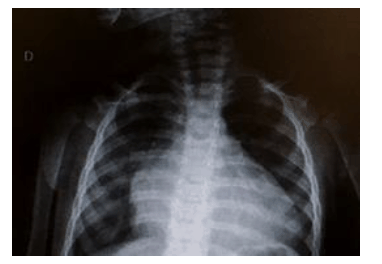

Uma paciente com onze meses de vida, previamente hígida e com história de cansaço há sete dias, foi levada para atendimento médico em duas ocasiões e medicada com sintomáticos. Sem melhora do quadro, chegou no pronto-socorro em regular estado geral, taquicárdica, com tiragem subcostal, taquipneia, saturação de oxigênio de 92% em ar ambiente, estertores crepitantes finos em ambas as bases pulmonares e fígado palpável a 3 cm do rebordo costal direito. Realizou um ecocardiograma, que evidenciou dilatação ventricular esquerda com fração de ejeção de 25%, e a radiografia de tórax mostrada abaixo.

Com base nessa situação hipotética, assinale a alternativa correta.